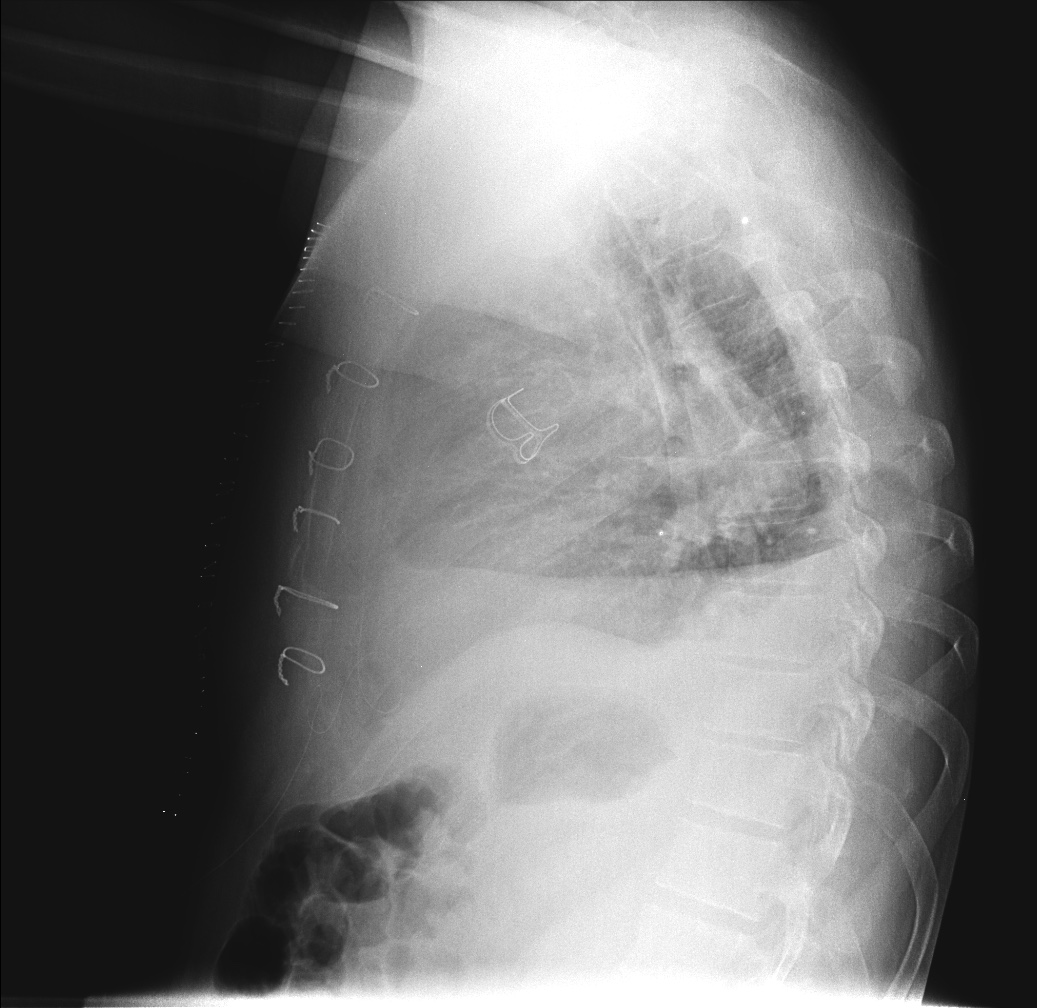

CASO: Febrícula y tos de 4 días de evolución.

Hallazgos:

- En la placa PA se observa una asimetría en los hilios pulmonares, el hilio izquierdo tiene una densidad aumentada.

- Tras examinar la placa lateral se observa un aumento de densidad en la columna que puede ser compatible con una condensación, es el signo de la desnificación vertebral.

SIGNO DE LA DENSIFICACIÓN VERTEBRAL: En la radiografía lateral normal, la densidad de la columna torácica tiende a disminuir desde la parte superior hasta el diafragma; la alteración de ese patrón por la presencia de una densidad superpuesta a la columna, indica la existencia de una consolidación pulmonar. Este signo adquiere especial valor cuando en la proyección posteroanterior la consolidación está oculta en el espacio retrocardíaco o en la base pulmonar.